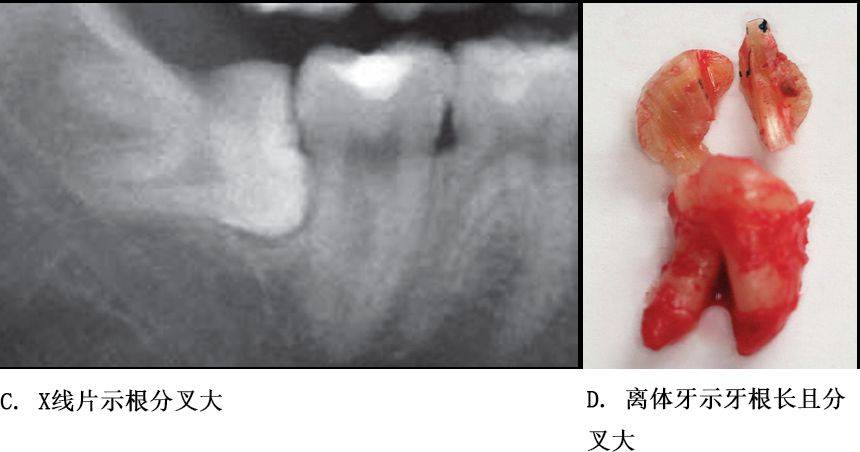

牙根阻力以多根牙、根分歧过大、特长根、U形根、牙颈部倒凹大者阻力较大根尖区以近中弯曲、多向弯曲、根尖肥大者牙根阻力较大。

根部阻力较大者的智齿形态